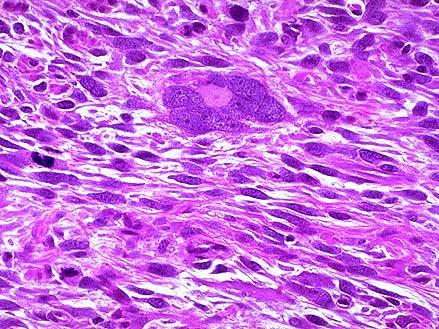

问题 女性,44岁,月经量多且不规律1年,腹痛6个月,下腹扪及包块,行手术切除。见子宫内壁粗糙,子宫肌壁间一6cm×5cm×5cm结节,质软,境界欠清,切面灰红灰黄,见局灶出血坏死。显微镜下如图,免疫组化DES(+)、CD10(-),应诊断为 ( )

选项 A.子宫平滑肌瘤 B.子宫平滑肌肉瘤 C.子宫内膜间质结节 D.子宫内膜间质肉瘤 E.子宫内膜癌

答案 B